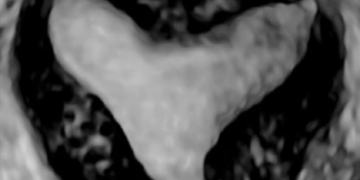

How To Do Luglio 2023: terminologia e classificazione MUSA

Cari soci, questo mese un nuovo video "How to do", dedicato alla terminologia e classificazione MUSA Grazie a Francesca Arezzo! Il video è accessibile ai soli soci SIEOG attraverso questo...